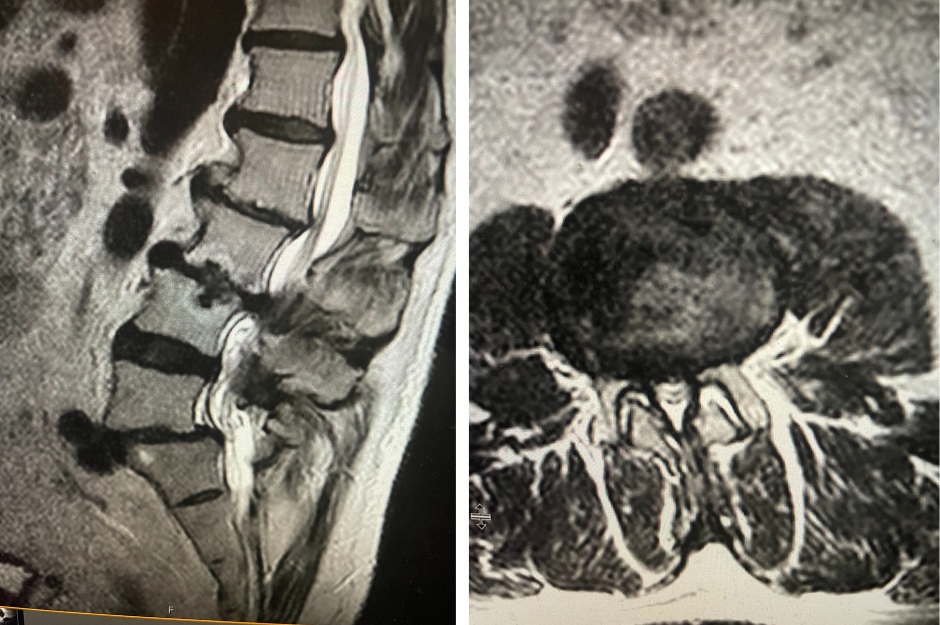

Figure 1. AP lumbar x-ray demonstrating degenerative lumbar levoscoliosis with secondary arthritic changes.

He had mild proximal weakness of his hip flexors. He also had a history of diabetes, hypertension, and hypercholesterolemia. Imaging studies were obtained. Plain x-rays (Fig. 1) demonstrated a degenerative levoscoliosis with the apex of the curve at L2-3. Lumbar MRI (Fig. 2) showed severe degenerative disc disease with an L5-S1 grade 1 spondylolisthesis and a significant retrolisthesis at L3-4 with severe lumbar stenosis.